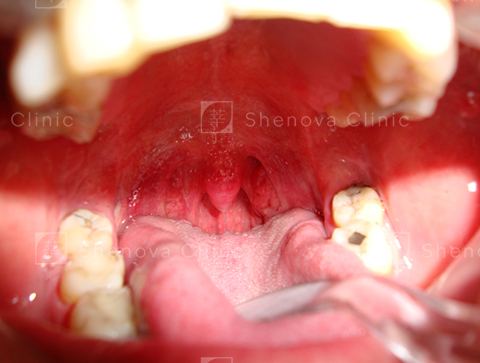

第二級_軟硬顎、扁桃腺、懸壅垂位置圖03

等級二

可見軟顎、少部分懸壅垂。